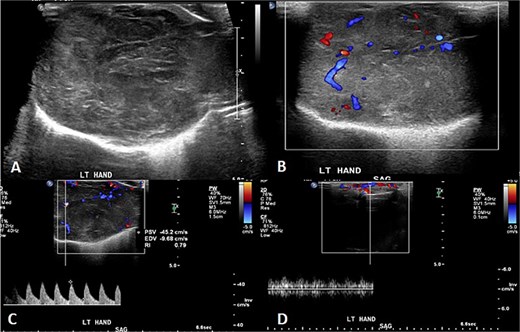

A 2-month-old girl was being followed for a suspected hemangioma on her left hand since birth. She was initially started on oral propranolol therapy but only received one dose, due to family concerns about possible side effects. The patient presented at the emergency room because of ulceration. It was observed clinically that the lesion had grown from 1.5 × 1.5 cm to 4 × 2 cm (Fig. 5). A biopsy of the lesion was taken. Ultrasound showed a partially defined large heterogeneously hyperechoic mass with internal vascularity on color Doppler with arterial and venous waveform giving atypical features of hemangioma (Fig. 6). Biopsy was done using FoundationOne Heme. The result showed stable microsatellite status and when we tested the tumor mutational burden, it showed two mutations per megabase. On MRI, a large lobulated subcutaneous soft tissue mass measuring 3.7 × 6.1 × 4.6 cm in dimensions was seen originating from the medial aspect of the left hand (Fig. 7). Internal flow voids, intermediate signal intensity on T1-weighted images, hyperintense signal on short tau inversion recovery (STIR)-weighted images, and noticeable heterogeneous enhancement on postcontrast sequences were all observed in the lesion. These imaging results raised suspicions of a malignant lesion.

Initial imaging utilizing gray scale and color Doppler US. (A) A gray scale US image showing a large heterogeneous lesion predominantly hyperechogenic in echotexture with a partially defined margin and (B–D) color Doppler US and spectral waveform showing internal vascularity within the lesion with the presence of arterial and venous waveform. The aforementioned findings are atypical for hemangiomas.